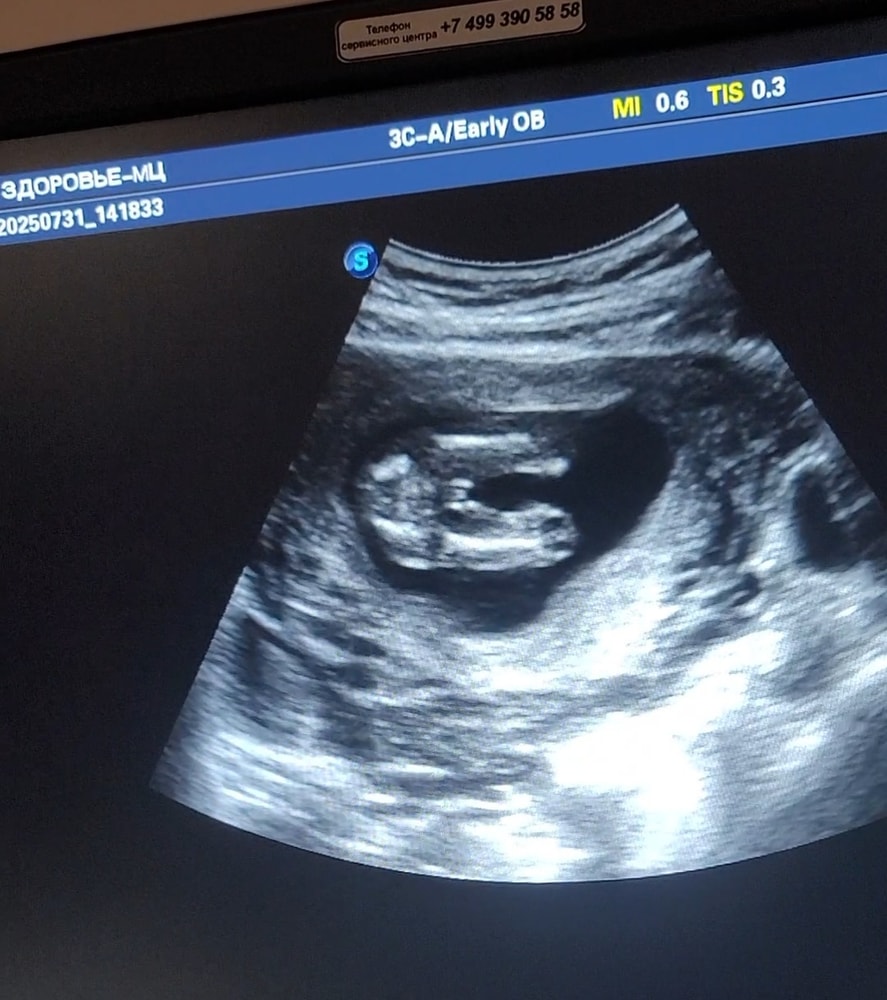

На первом скрининге тоже предположили девочку, через несколько дней пришел НИПТ - мальчик))) ну и на узи в 16 недель, уже тоже однозначно подтвердили мальчика)

У меня в ту Б такой же отросточек был на первом скрининге, сразу сказали мальчик 100% ))) в эту Б ждать и гадать не хочу, сдам кровь на пол и всё)